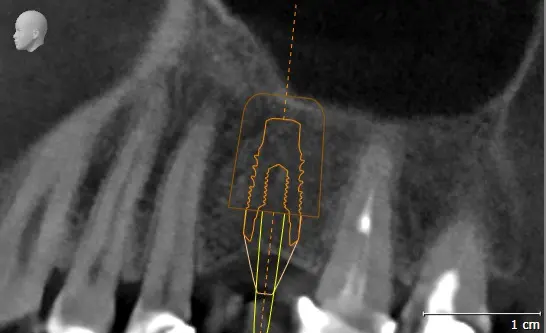

TOMOGRAFÍA PARA ENDODONCIA

Evaluación necesaria en campo reducido para visualizar los conductos radiculares o probables fracturas.